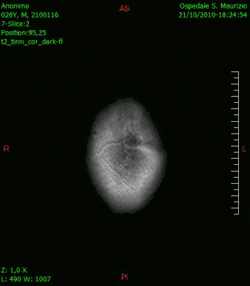

-

Animación en el plano sagital de un caso de resección total gruesa de un glioblastoma -

Animación en el plano axial -

Animación en el plano coronal